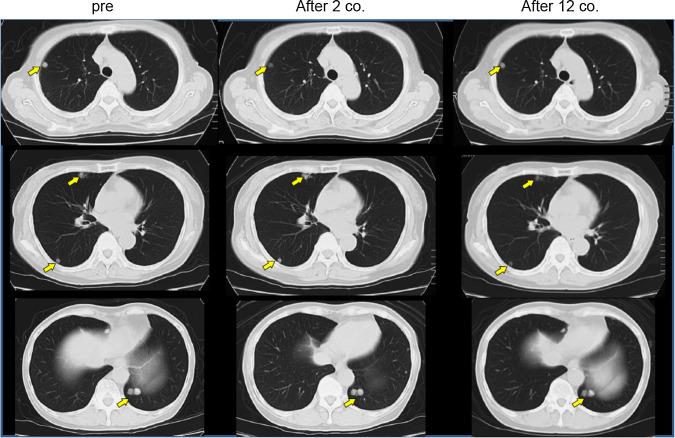

Vaccinations with HIG2-9-4 peptide could be well tolerated without any serious systemic adverse events. Peptide-specific cytotoxic T lymphocyte (CTL) responses were detected in eight of the nine patients. Doses of 1.0 or 3.0 mg/body seemed to induce a CTL response better than did a dose of 0.5 mg/body, although the number of patients was too small to draw a firm conclusion. The disease control rate (stable disease for ≥4 months) was 77.8 %, and the median progression-free survival time was 10.3 months.

用HIG2 - 9 - 4肽进行疫苗接种耐受性良好,未出现任何严重的全身性不良事件。9例患者中有8例检测到肽特异性细胞毒性T淋巴细胞(CTL)反应。尽管患者数量太少无法得出确凿结论,但1.0或3.0 mg/体的剂量似乎比0.5 mg/体的剂量更能诱导CTL反应。疾病控制率(疾病稳定≥4个月)为77.8%,无进展生存期的中位数为10.3个月。